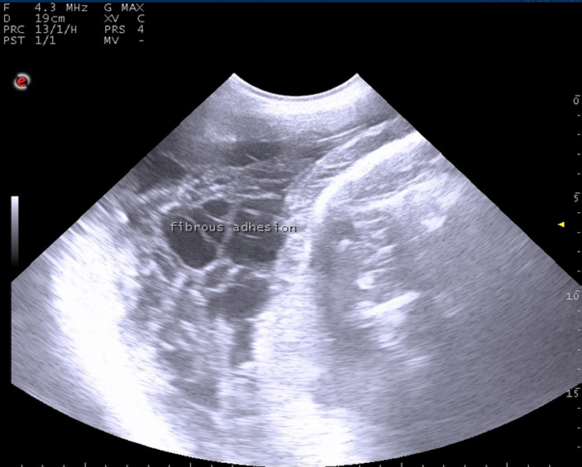

Out of the 75 uterine torsion affected cases, fifty buffaloes (66.67%) responded successfully to the rolling procedure, and followed by complete cervical dilatation and vaginal fetal delivery (Table 1), while 17 buffaloes (22.67%) responded successfully to the rolling procedure and followed by incomplete cervical dilatation. And only eight buffaloes (10.67%) failed to respond to the rolling procedure due to the presence of uterine adhesion with adjacent organs, so these animals were culled due to extensive parametritis and peritonitis after ultrasonographic examination (Fig. 1).

Fig. 1. Ultrasonographic examination with trans-abdominal probe at frequency 3.5–5 MHZ showing long standing uterine torsion case with severe degree at full term suffered from failure of detorsion due to presence of uterine adhesion with fibrin threads.